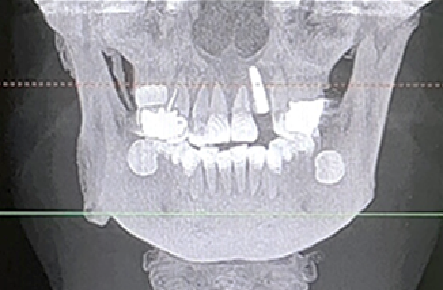

术前CBCT

21颊侧牙槽骨吸收至根尖,腭侧牙槽骨吸收至根尖1/3,根周可见低密度影。牙槽嵴宽度6.41mm。

局部反合、患牙长期牙周病变,骨质缺损,但软组织无明显缺失,为II类拔牙窝形态。

22冠状位CBCT情况

唇舌牙槽嵴宽度6.41mm,垂直骨缺失1/2,软组织无垂直向缺失。